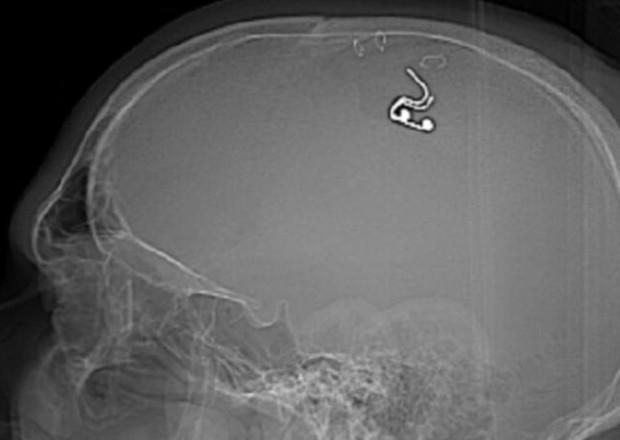

Rusiyada bir şəxs yuxularını idarə etmək üçün beyninə çip taxmaq məqsədilə başını deşib.

32gun.az xəbər verir ki, Mixael Raduqa adlı kişi başına məişətdə istifadə olunan deşici alət vasitəsi ilə yuxularını idarə etməyə imkan verən çip yerləşdirib.

Saatlarla internetdə neyrocərrahların necə işlədiyini göstərən videolara baxdığını deyən Raduqa "Telegram"dakı paylaşımında “Qazma apardım, başımda deşik açdım və beynimə elektrod yerləşdirdim”,-deyə bildirib.

O, bu görüntüləri "Twitter" səhifəsində də paylaşıb və bildirib ki, əməliyyat zamanı az qala qanaxmaqdan ölsə də, nəticələr gələcək yuxuların idarə olunması üçün böyük ümidlər açır.